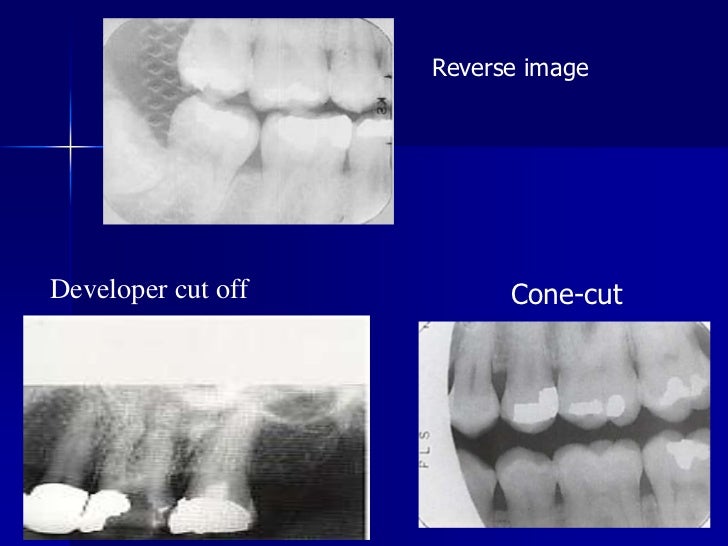

Radiographic errors and artifacts Dental Xray Errors The ada recently released new guidance in jada on safety and regulatory aspects of radiography, which updates portions. Improper time selection is the most likely error. Learn how to avoid and correct common errors in intraoral radiography, such as placement, alignment, and angulation. Table 5 lists various errors that can occur with panoramic imaging. Incorrect exposure can be caused by. Dental Xray Errors.

Errors in xray film processing l oral radiology MCQs for dental Dental Xray Errors Learn how to avoid and correct common errors in intraoral radiography, such as placement, alignment, and angulation. Improper time selection is the most likely error. It is important for the clinician to be able to understand errors when they occur and how to correct them. Table 5 lists various errors that can occur with panoramic imaging. The most common being. Dental Xray Errors.